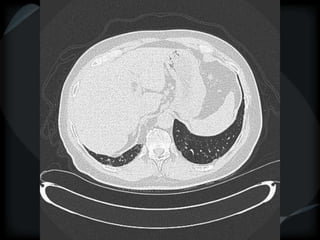

Septal Pattern – lymphatic/venous

● Smooth – pulmonary veno-occlusive disease, mitral

stenosis, capillary hemangiomatosis, LC

● Beaded – lymphangitic carcinomatosis, lymphoma,

lymphangiomatosis, sarcoid

Rare = non-Langerhans’ cell histiocytosis (bone+pleura)

amyloidosis

PHTN – PA 39mm

39.2mm

PHTN and septal thickening

? PVOD